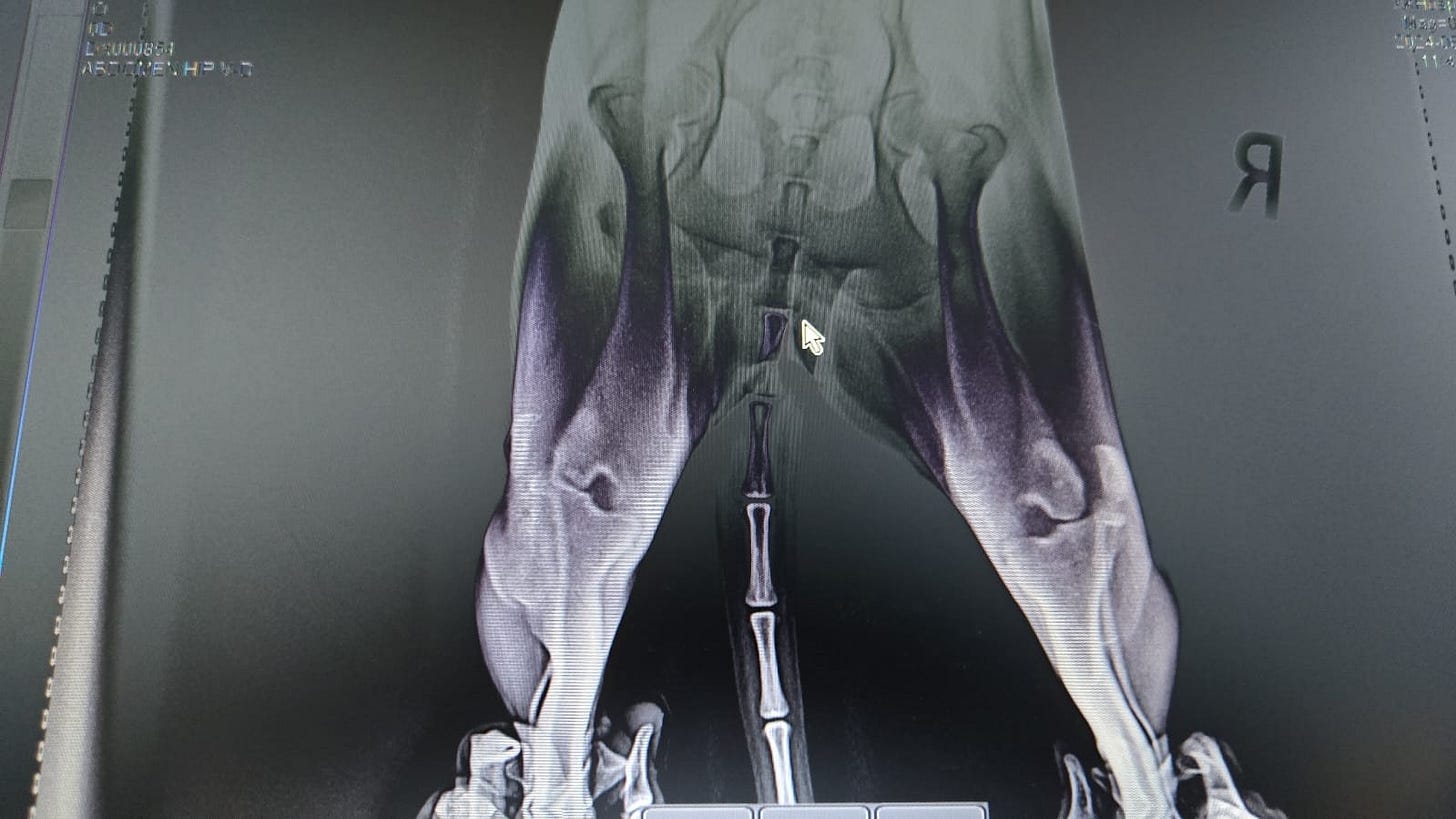

Someone had slammed her back end into the ground with the force of a boot. The trauma forced both her knees sideways.

Under the guidance of a university professor of veterinary medicine, our orthopedic surgeon performed a complex and delicate operation to repair the damage. The surgery itself was a success, and for a brief time, there was hope that she might reclaim some of the life stolen from her.